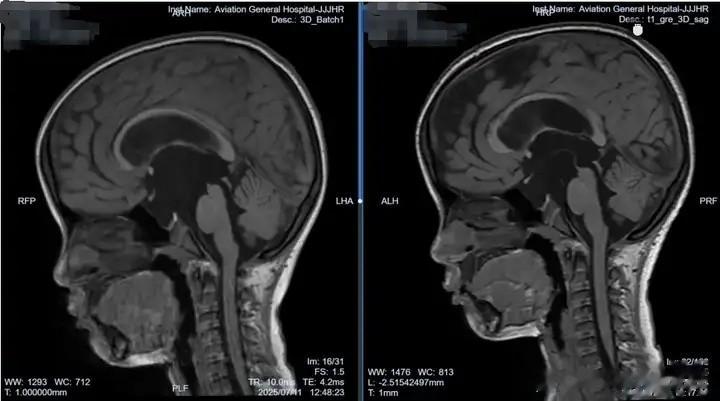

2024年6月,3岁的小妍(化名)在睡眠中突发全身抽搐,表现为颜面部肌肉及肢体节律性痉挛式抖动,呼之不应,持续时间约 8-9 分钟。紧急送往当地医院后,测体温 38.3℃,被考虑为 “高热惊厥”,给予镇静、退热治疗。随后的头颅 CT 及 MRI 检查发现脑室系统明显扩张,当地医院建议行脑室腹腔分流术,但小妍父母因担忧终生带管风险选择保守观察。2025年4月,小妍再次出现类似抽搐症状,复查显示脑积水持续存在。小妍父母了解到北京航空总医院的肖庆教授是治疗脑积水等相关疾病的专家,慕名前往北京求医。

肖庆主任详细查看小妍的影像资料后指出,这并非普通的脑积水,而是由于鞍上池囊肿堵塞了脑脊液循环通路所致。鞍上池位于颅内脑脊液循环的关键通路附近,当囊肿增大时,可能直接压迫或阻塞脑脊液的正常循环通道,导致脑脊液无法顺利从脑室系统流向蛛网膜下腔被吸收,从而形成梗阻性脑积水。如果直接进行脑室 - 腹腔分流手术,而忽略了鞍上池囊肿占位的情况,会使原本的制约关系失去平衡,脑室压力降低的同时,可能导致蛛网膜囊肿加剧扩张,往后处理会越来越棘手,还增加了分流术后的并发症风险。

肖庆主任建议采用软性神经内镜手术来解决囊肿问题。软性神经内镜手术具有创伤小、视野清晰、可灵活到达病变部位等优势,骨孔直径不到 1cm。在完善脑电图等检查后,于既定手术日,肖庆主任团队为小妍在全麻下行神经内镜检查术 + 脑室 - 囊肿 - 基底池造瘘术,术后病情平稳,复查MRI显示:脑室回缩、囊肿塌陷,于术后一周好转出院。